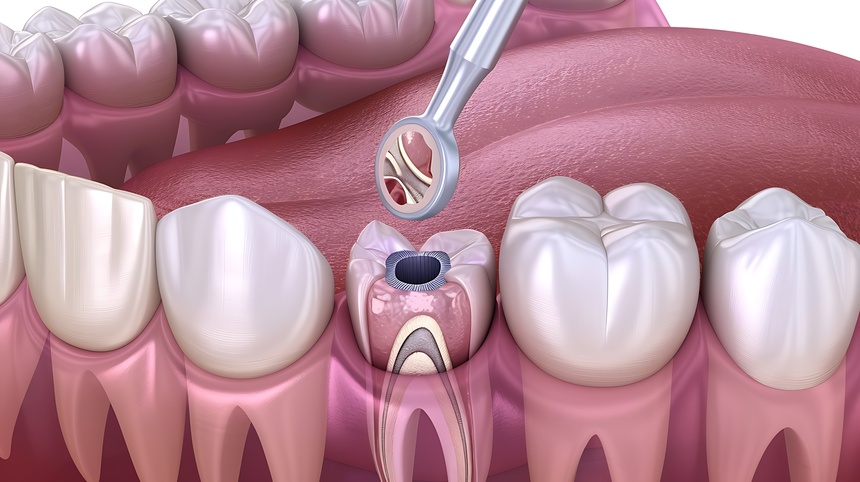

Painless Root Canal Treatment in College Road Nashik

A root canal is a dental procedure designed to treat infected or damaged tooth pulp. Traditionally associated with disco...

Painless Root Canal Treatment in Canada Corner Nashik

A root canal treatment is often associated with pain and discomfort, but modern dental advancements have made it a painl...